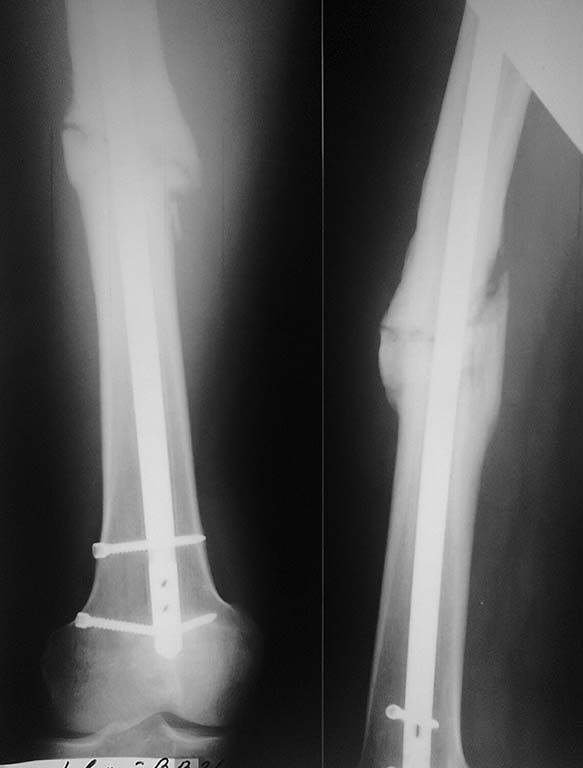

[Ortho] Удаление погнувшегося винта

Год.Собираемся рассверлить и реостеосинтезировать.